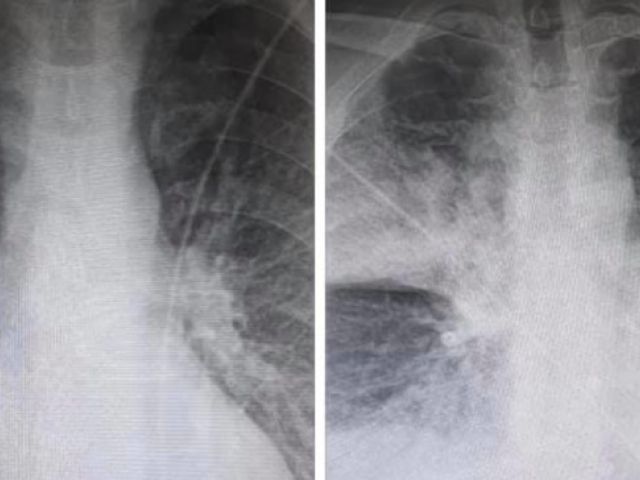

23 Σεπτεμβρίου, 2020 Press Room NEA Κορωνοϊός: Aκτινογραφία δείχνει τη ραγδαία επιδείνωση στους πνεύμονες 38χρονου ασθενούς [εικόνα]